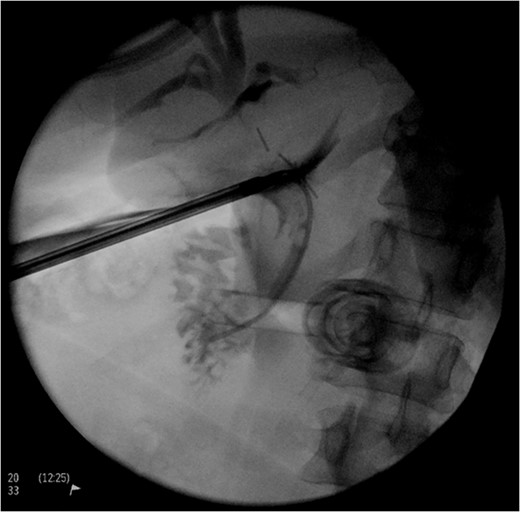

Intraoperatively, the biliary anatomy was distorted by chronic inflammatory change, and a critical view of safety was not able to be achieved. When attempting to clear the hepatocystic triangle, a window was made around the structure believed to be the gallbladder infundibulum. There was no artery identified entering the gallbladder. To help facilitate identification of structures, a cholangiogram was performed. A ductotomy was made with laparoscopic scissors below the infundibulum presumed to be cystic duct, and a catheter inserted into the duct which was secured with a cholangiography clamp. About 20 mL of 50–50 mixture of saline and iodinated contrast was injected under fluoroscopy (Fig. 1). This revealed proximal filling with hepatic trifurcation from a common confluence, and distal flow into the duodenum without evidence of a cystic duct, and thus identified a ductotomy through the common bile duct. A second surgeon was called into the operating theatre for confirmation of findings, and the ductotomy was closed laparoscopically with Polydioxanone (PDS) sutures. ‘Fundus first’ dissection revealed a small 1.5 cm gallbladder and confirmed no discernible cystic duct (Fig. 2). There was no impacted stone to suggest a Mirizzi syndrome. A PDS endoloop was placed around the gallbladder at the junction of the bile duct, and a drain placed in the subhepatic space. Figure 3 demonstrates the small operative specimen.

(A) Intraoperative view following cholangiogram. (B) Intraoperative view following fundus-first approach.